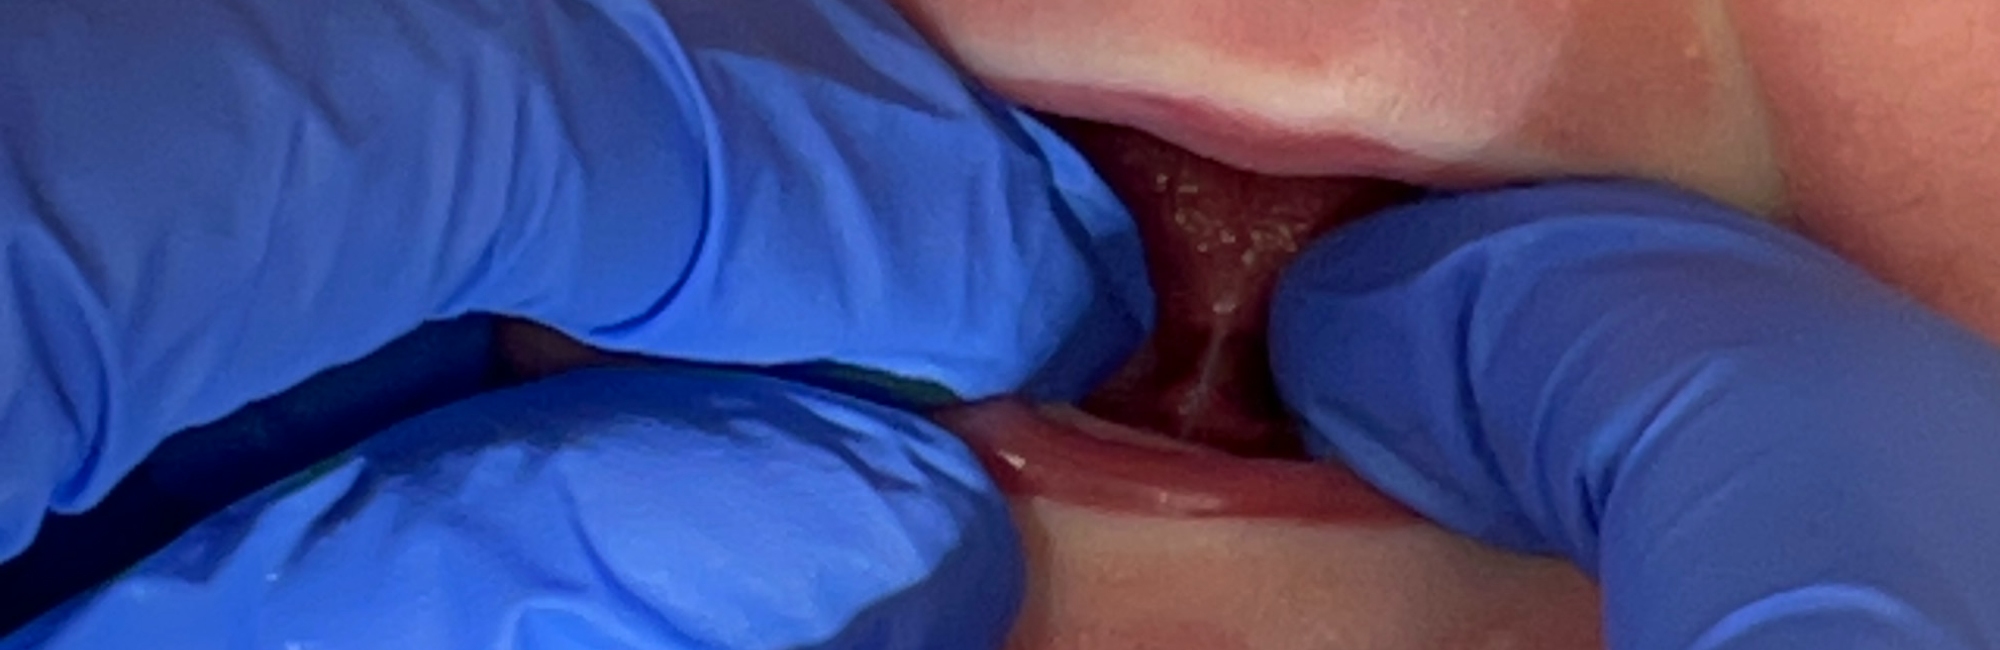

The image above is of a baby who had been referred with concern about tongue-tie, but who has a normal variation of lingual frenula. The baby and her mother had fit and hold problems whilst breastfeeding, which resolved with implementation of the gestalt method.

Although many infants have a prominent and membranous frenulum, which may attach anywhere along the ventral surface of the tongue, a tongue-tie is a variation of frenulum which may attach close to the tip of tongue, often to the alveolar ridge instead of the floor of the mouth, and is assessed clinically as impacting on the infant’s capacity to suckle without causing maternal nipple pain.